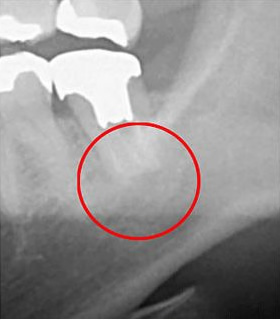

次の画像は、同じ患部をCTとレントゲンで撮影した画像です。

左の写真がCTで、右の画像がレントゲンで撮影したものです。

赤丸で囲んだところには、黒い影が見えます。ここには炎症が起こっているのですが、右の写真には影がありません。

レントゲン写真だけの診断だと、この炎症は見逃されてしまう可能性が高いです。気づかずに放置していれば炎症は悪化し、抜歯になってたかもしれません。

当院はこのような見逃しを防ぐために、CTによる診断を徹底しています。